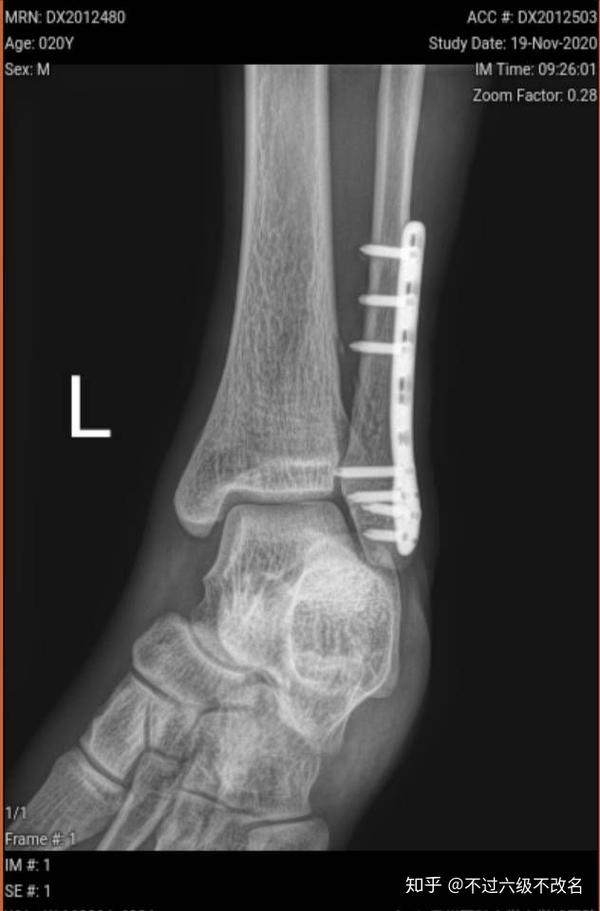

脚踝骨折近一年的恢复情况 知乎

踝关节骨折病例 请问腓骨是否需要复位固定 骨科专业讨论版 丁香园论坛